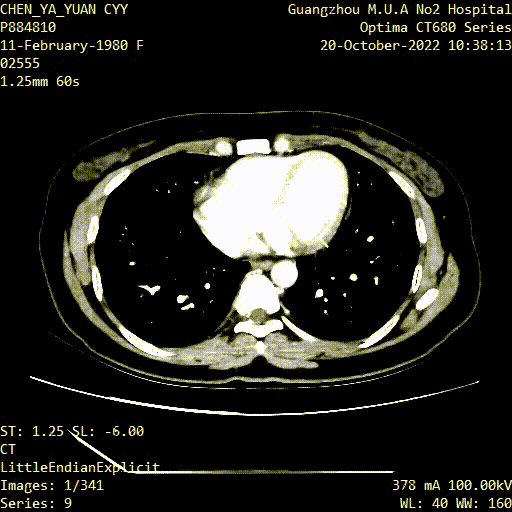

Case 2

男性,55岁

因“下腔静脉滤器留置2月”入院

患者2月前因“肺动脉栓塞”在外院行下腔静脉滤器植入术,1周前外院腔内取滤器失败

查体:双下肢皮温暖,无肿胀,非凹陷性,双股动脉、腘动脉、足背动脉搏动可及。

既往史:3月前因车祸致右肩胛骨骨折,已行内固定术。

入院彩超:下腔静脉及双下肢静脉无血栓

图为:术后1月腹部CT及增强扫描